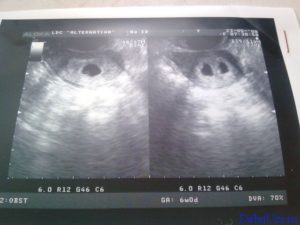

Объективным сроком, на какой неделе визуализируется два плода, считается пятая неделя с момента зачатия. На экране монитора ультразвук показывает два темных пятна в маточной полости. По мере формирования малышей картинка будет меняться. Когда детей двое, они, как правило, немного отстают по фенометрии (определение размеров посредством УЗИ).

Двойняшки покажутся на УЗИ уже с 5 недели

В таком случае УЗИ эмбрионов покажет наличие двойни уже на 5 неделе, особенно с применением высокочувствительных датчиков 3д-сканирования. Осмотр дает возможность определить двойняшек только на сроке 9-11 недель.

Следовательно, наличие двойняшек в утробе выявляется посредством ультразвука уже через месяц после зачатия, на снимке они выглядят как 2 образования темного цвета внутри полости матки (см. фото УЗИ-обследования двойни ниже).

- УЗИ-диагностика двойни через 11 недель показывает немного уменьшенные для своего срока развития размеры первого и второго плода – примерно 4,2-4,8 см.

- При обследовании на 12 неделе эмбрионы имеют длину по 6 см, а их вес составляет примерно 8 грамм.

Увидеть двойню на УЗИ при беременности можно уже через месяц после зачатия. В этом случае специалист отметит на экране монитора два пятна черного цвета, которые хорошо просматриваются ультразвуком